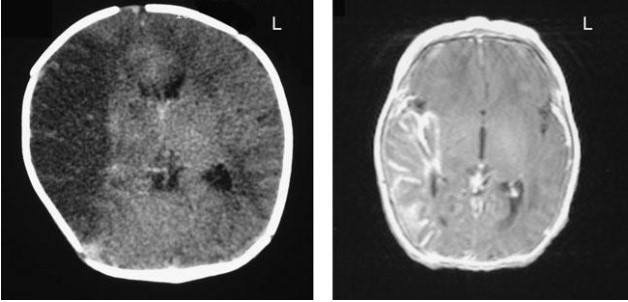

Major brain regions and their functions:

Circle of Willis: